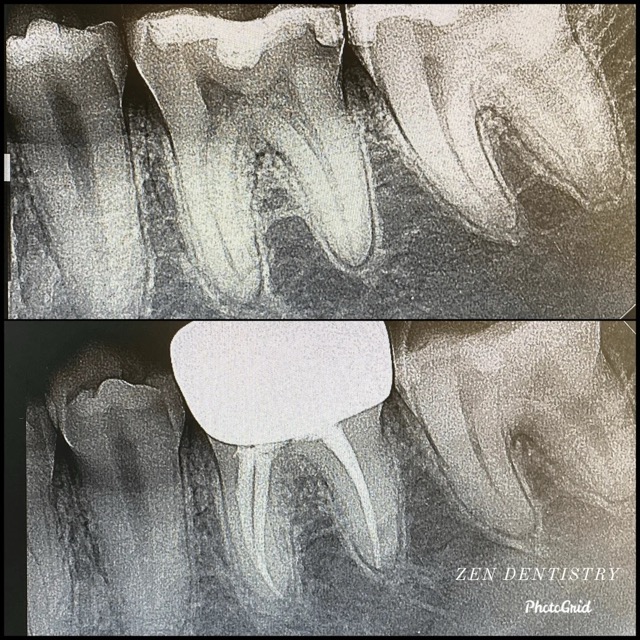

Patient presented with a complaint of severe constant pain that would exaggerate on laying down and biting. Patient wanted to save the tooth. A thorough clinical exam, endodontic screening and proper x rays led to the diagnosis of necrotic (dead) pulp due to dental caries with inflamed periodontal ligaments.

Our Dentists used the latest technology and highest quality products to finish this beautiful root canal. The tooth was crowned after the root canal to restore function and aesthetics.